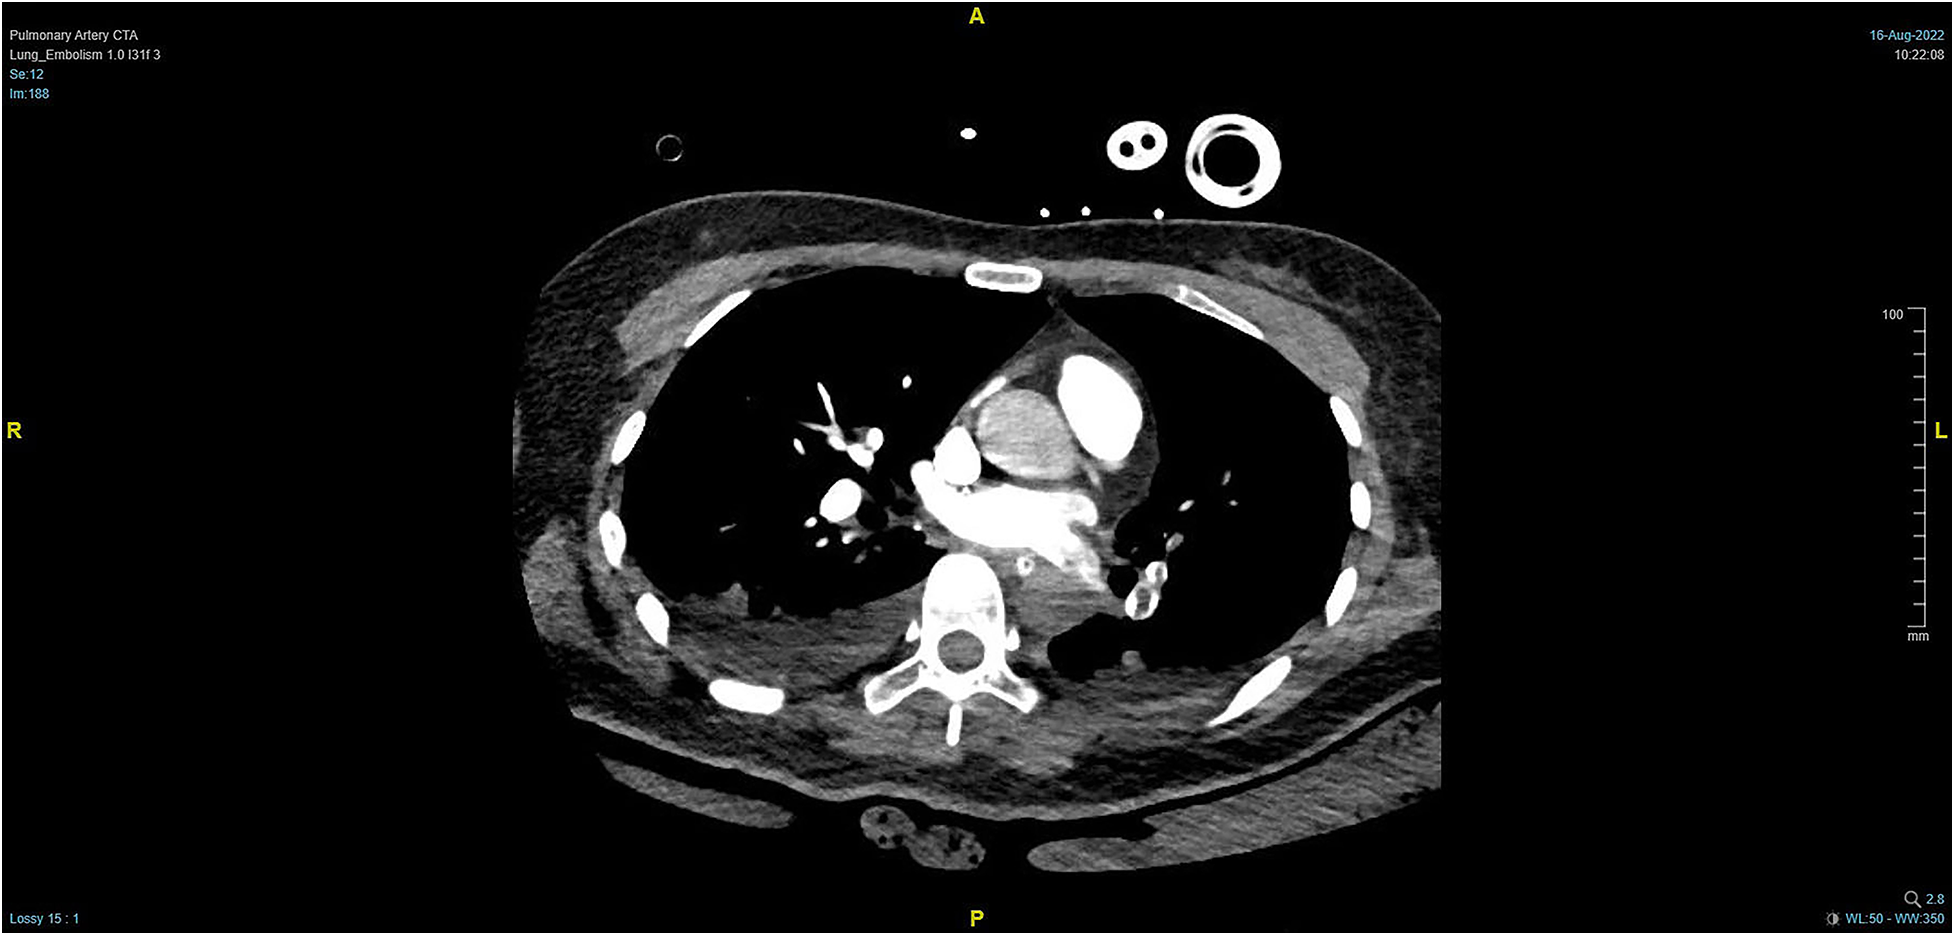

Figure 4

PTCA on Day 2 after operation indicating strip-shaped filling defects in multiple branch arteries of the upper, middle, and lower lobes of the right lung and the lower lobe and lingular segment of upper lobe of the left lung, and multiple pulmonary artery embolisms in both lungs.

During the procedure to surgically resect the right renal malignancy, the patient experienced decreased blood pressure, low-tidal carbon dioxide and high partial pressure of carbon dioxide in blood gas. After identifying a pulmonary embolism, the hepatobiliary surgeon performed a successful inferior vena cava embolectomy. The hemodynamics was still unstable after the surgery, with high pressure in the pulmonary artery, and the transesophageal ultrasound imaging revealed right ventricular dilation and strain, as shown in Figure 3. The ECMO team determined the indications for VA-ECMO assistance. Then, the right femoral artery was punctured immediately by inserting a 19 F cannula and the femoral vein was punctured by inserting a 21 F cannula. VA-ECMO was successfully established, thereafter, the respiratory status stabilized, and the patient was referred to the Department of Critical Care Medicine. The postoperative pulmonary artery computed tomography angiography (CTA) revealed strip-shaped filled defects in multiple branch arteries of the upper, middle, and lower lobes of the right lung, and the lower lobe and lingular segment of upper lobe of the left lung, and multiple pulmonary artery embolisms in both lungs (Figures 4, 5). Given the extensive embolization of the tumor in this patient, severe pulmonary hypertension may have developed earlier. Therefore, after comprehensive consideration, stronger drugs such as milrinone, ambrisentan, and treprostinil were given to reduce pulmonary artery pressure, along with VA-ECMO support.